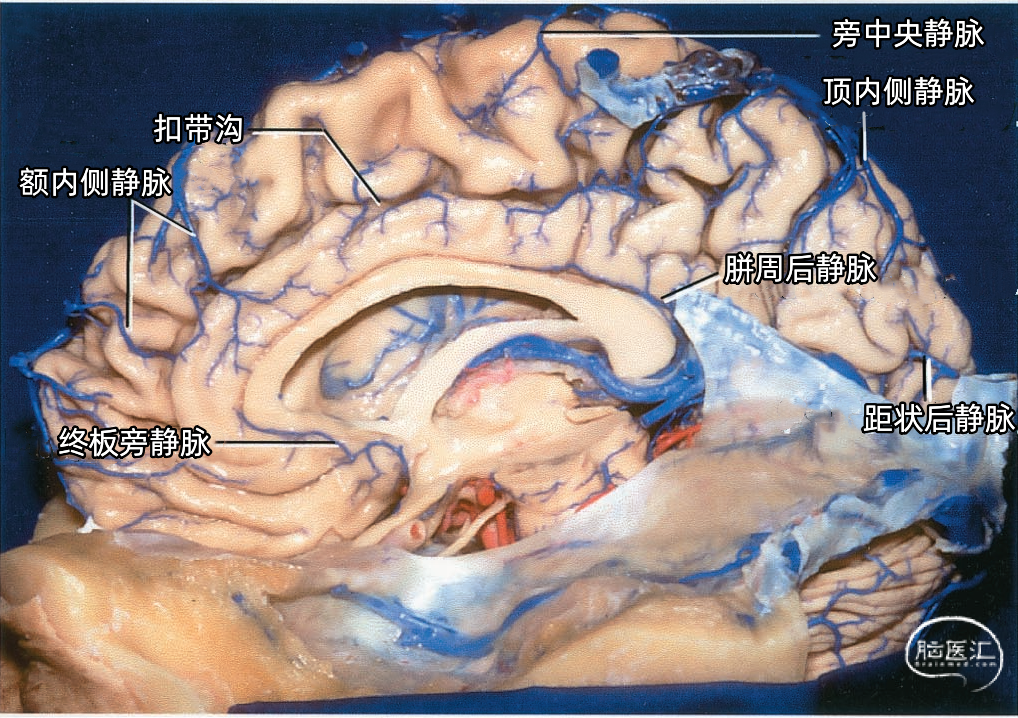

下矢状窦(inferior sagittal sinus 下图)夹于大脑镰游离缘中,前方起自盲孔,向后注入直窦。下矢状窦直径为2mm左右,最短者仅19mm,长者可达110mm,平均长度70mm,其腔内无蛛网膜颗粒。主要收集大脑镰、胼胝体和扣带回附近的静脉血。

下矢状窦较上矢状窦细小,前部窦腔管径细、后部管径粗,移行于直窦处有大脑大静脉汇入。上矢状窦有可能通过大脑镰内的静脉通道与下矢状窦交通,这一连接偶尔很大,以至于上矢状窦主要引流入下矢状窦和直窦。 下矢状窦起端变异大,常不出现于前颅窝内。常将大脑镰游离缘分为前、中、后三段,约一半下矢状窦起始于中1/3段,约1/2下矢状窦始于后1/3段,有极少者缺如。在颅前窝手术中,大脑镰连同上、下矢状窦均可切断,而不出现神经缺损症状。 胼周前静脉是下矢状窦最大的属支。下图示额内侧静脉引流扣带沟以上区域,汇入上矢状窦。胼周前静脉汇入下矢状窦前端。 下图示额内侧静脉和顶内侧静脉引流半球内侧的外侧区并汇入上矢状窦。引流扣带沟面对胼胝体部分的静脉进入胼周前静脉、胼周后静脉、终板旁静脉和大脑大静脉。引流距状沟后部的距状后静脉通常汇入半球外侧面的静脉。一支小的胼周后静脉汇入Galen静脉,来自围绕在胼胝体周围的扣带沟的静脉通常汇入终板旁静脉或胼周静脉。扣带回和胼胝体静脉与下矢状窦的结合部经常形成尖鱼钩样弯曲,尖端向前。

▼2.大脑内侧面静脉的引流区

额叶内侧面(蓝色)由终板旁静脉、额前内侧静脉、额中内侧静脉,额后内侧静脉、胼周前静脉、旁中央静脉引流。

顶叶内侧面(黄色)由旁中央静脉、顶前内侧静脉、顶后内侧静脉、胼周后静脉引流。

枕叶内侧面(紫色)由距状前静脉、距状后静脉引流。

大脑内侧面静脉的引流方向

额叶内侧面的静脉按引流方向由两种蓝色标出:浅蓝色为上升静脉,进入上矢状窦。深蓝色为下降支,汇入下矢状窦和大脑前静脉、基底静脉。

升支包括额前内侧静脉、额中内侧静脉、额后内侧静脉和旁中央静脉。降支包括终板旁静脉和胼周前静脉。

顶叶内侧面的静脉按引流方向由两种红色标出:浅红色为上升静脉,进入上矢状窦。深蓝色为下降支,进入Galen静脉及其属支。

升支包括旁中央静脉、顶前内侧静脉、顶后内侧静脉。降支为胼周后静脉。

枕叶内侧面的静脉按引流方向由两种紫色标出:浅紫色为上升静脉,进入上矢状窦。深紫色为下降支,进入Galen静脉及其属支。

升支包括距状后静脉和进入深静脉系统的距状前静脉。